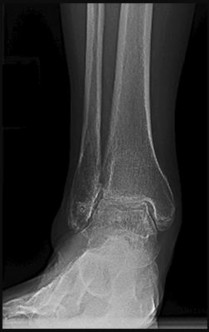

Figures 1 and 2 are the radiographs of a 68-year-old woman who comes to the emergency department after stepping into a hole and twisting her ankle. She is complaining of isolated ankle pain and is unable to bear weight.

The radiographs reveal a trimalleolar ankle fracture dislocation with an associated distal tibiofibular syndesmotic disruption. Medial and lateral malleolar stabilization are consistently agreed upon. The decision to stabilize the posterior

malleolus is more controversial. Posterior malleolar stabilization accomplishes the following:

9. Restores incisura competence thereby reducing the incidence of syndesmotic malreduction by creating containment

10. Assists in stabilizing the syndesmosis via the posterior inferior tibiofibular ligament, potentially limiting the need for additional syndesmotic stabilization

11. Maximizes the surface area for ankle joint loading

12. Enhances posterior translational stability of the talus

The traditional indication for stabilization of the posterior malleolus is based on fragment size. However, fracture orientation varies and makes evaluation of the fragment size challenging with a lateral radiograph alone. The three primary types include the posterolateral oblique, medial extension, and shell. Because of the additive syndesmotic stability which is gained through the deep deltoid ligament and medial malleolar fixation, the anterior talofibular ligament and lateral malleolar fixation, and the posterior inferior tibiofibular ligament and posterior malleolar fixation, syndesmotic stability should only be assessed after all other points of instability that are planned for fixation are fixed.

Syndesmotic instability should be assessed with direct manipulation on both the anteroposterior and lateral views with special attention to the lateral view. Syndesmotic reduction should be assessed either through open visualization or by comparing closed reduction parameters (clear space, overlap, and fibular position on the lateral view) with the patient’s contralateral side (assuming no injury). This is more effective than using population norms secondary to the two types of syndesmotic morphologies which create different absolute values for these parameters.